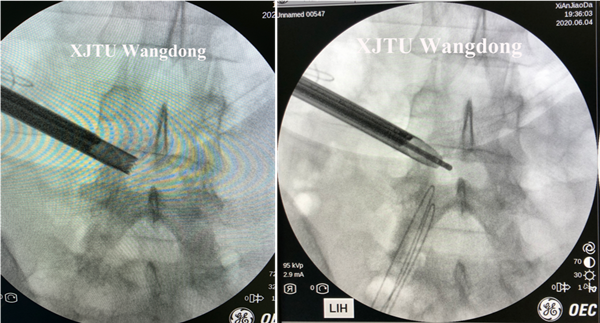

经病友介绍,李女士慕名来我院,就诊于骨二科(脊柱外科)王栋教授,在经过详细的询问病史、查体及影像学检查分析后,王教授建议患者进行脊柱内镜手术。入院后,完善患者术前检查,王栋教授、赵波、秦杰副教授治疗组根据患者临床资料制定了详细的治疗计划,包括术中镇静,局麻药的种类、浓度、用量,手术患者体位及舒适度,术前镇痛,术中与患者交流,影像学定位,靶点技术,椎间盘摘除的程度,神经根减压的范围,出血的处理,术后下床活动时间及康复治疗注意事项,术后随访等。入院后第3天行局麻下全脊柱内镜腰椎间盘突出症髓核摘除减压术,应用脊柱内镜I See系统,顺利完成手术,手术时间50分钟,出血约20ml,患者全程无明显疼痛,术后腰及右下肢症状消失,第二天离床活动,住院5天出院,随访6月,情况良好。

孔径手术的术中定位